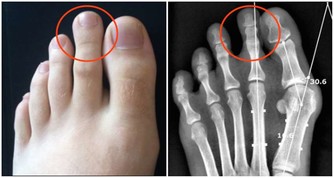

在我們的腎臟當中,腎小球有著過濾的作用,而腎小管能夠幫助吸收,但是隨著年齡的不斷增長,身體各項器官機能逐漸衰退,腎臟當中的這兩個零件也會逐漸老化,導致尿液濃縮濃度減退,從而出現這些問題。